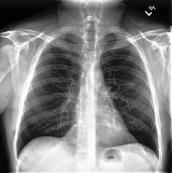

Large numbers of labeled medical images are essential for the accurate detection of anomalies, but manual annotation is labor-intensive and time-consuming. Self-supervised learning (SSL) is a training method to learn data-specific features without manual annotation. Several SSL-based models have been employed in medical image anomaly detection. These SSL methods effectively learn representations in several field-specific images, such as natural and industrial product images. However, owing to the requirement of medical expertise, typical SSL-based models are inefficient in medical image anomaly detection. We present an SSL-based model that enables anatomical structure-based unsupervised anomaly detection (UAD). The model employs the anatomy-aware pasting (AnatPaste) augmentation tool. AnatPaste employs a threshold-based lung segmentation pretext task to create anomalies in normal chest radiographs, which are used for model pretraining. These anomalies are similar to real anomalies and help the model recognize them. We evaluate our model on three opensource chest radiograph datasets. Our model exhibit area under curves (AUC) of 92.1%, 78.7%, and 81.9%, which are the highest among existing UAD models. This is the first SSL model to employ anatomical information as a pretext task. AnatPaste can be applied in various deep learning models and downstream tasks. It can be employed for other modalities by fixing appropriate segmentation. Our code is publicly available at: https://github.com/jun-sato/AnatPaste.